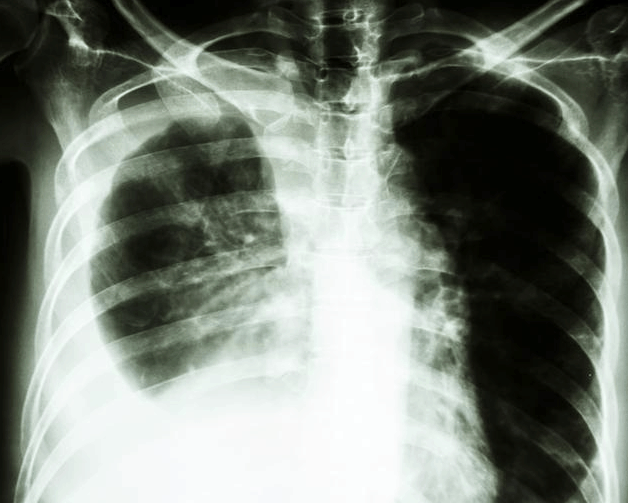

可是检查结果却让她彻底没了神,医生叹息:你来太晚了,都已经是肺癌晚期了,怎么能咳嗽4个月才来医院呢!对自己的身体太不负责任了。

2、肺癌引起的咳嗽

”肺癌形成之初,大多无声无息,如果出现没有明显诱因的咳嗽,特别是干咳、刺激性咳嗽,无痰,咳嗽昼夜不停,服用了药物后超过半个月不好,就要特别小心,可能不是感冒咳嗽那么简单,就要当心肺癌了。

3个症状可能是肺癌,要注意了!

1、刺激性呛咳

这种咳嗽往往没有什么规律,一咳嗽就抑制不住,也停不下来。就像吃饭的时候一不小心,呛了一粒米的感觉。其实咳嗽是肺癌患者最早和最常见的症状。但由于起病时症状类似感冒,所以很容易被忽视。

2、胸痛、呼吸困难

肺癌早期的胸痛没有什么规律性,就是那种能够忍受的钝痛;但如果到了晚期,就会出现无法忍受的疼痛感。